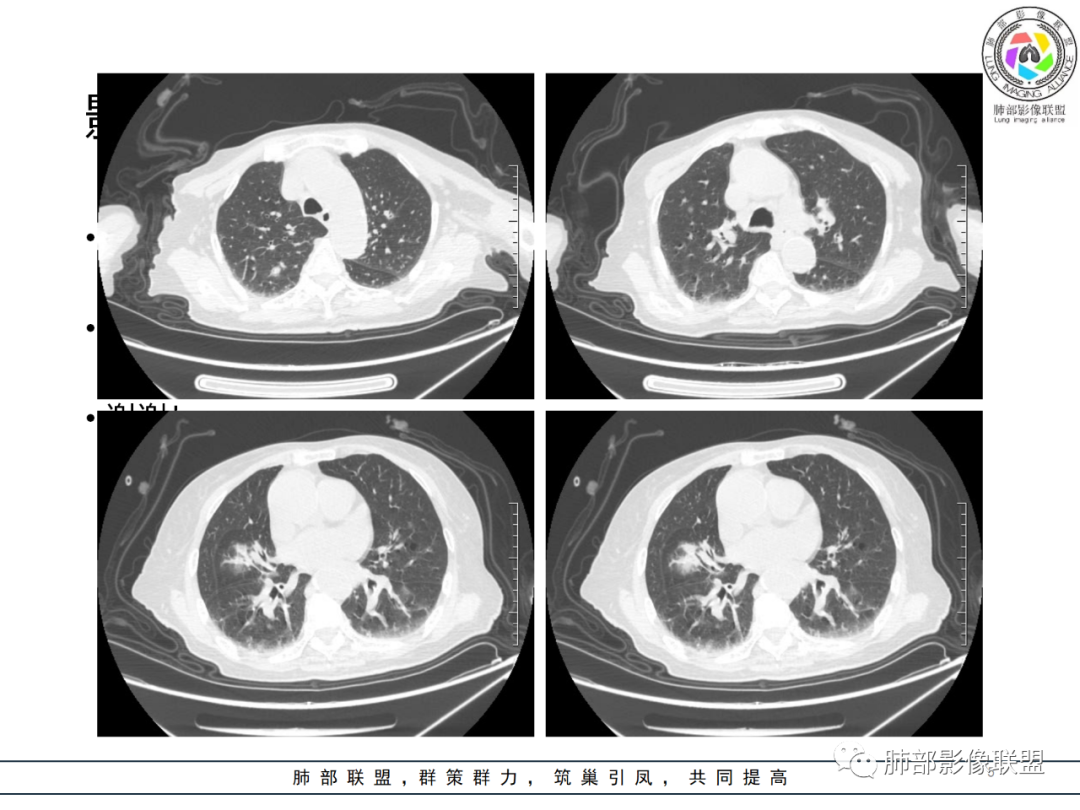

影像资料

老年女性,发热起病,两肺散在斑片状影,三个月后两肺病灶进展,支气管血管束增厚,结合发热病史、实验室检查LCH增高,肾脏及腹膜后淋巴结肿大,结合以上综合考虑符合淋巴瘤表现。

老年女性 3个月前发热,双肺支气管血管束增粗改变。3个月后再次发热,影像见双肺广泛支气管血管束明显增粗,较前进展,并延续进入纵隔,另外增强见双肾周增多软组织密度,左肾明显且肾门处形成肿块样改变。综合考虑肿瘤性病变可能性大,1.小圆细胞肿瘤类病变,淋巴瘤?2 全身组织细胞类病变,如ECD,需要看看骨组织有无问题。3 左肾恶性肿瘤并淋巴道播散,如弥漫性尿路上皮癌。最后考虑 淋巴瘤>ECD>左肾恶性肿瘤并转移。

老年女性,发热,白细胞不高,CRP增高,LDH增高,糖尿病。两肺支气管血管束周围实变、GGO,支气管相对通畅,提示淋巴间质或血管来源。三个月明显进展伴双肾浸润性病变、腹膜后淋巴结肿大,轻-中等程度强化。考虑淋巴瘤,鉴别系统性疾病(IgD4、血管炎)。

82岁女性,反复发热入院,查外周血白细胞升高,抗生素治疗可缓解,支持细菌感染性发热,结合肾脏肿瘤,考虑泌尿系感染发热;CT提示双肺多发毛玻璃影,右下肺多发大结节影,3月复查,双上肺毛玻璃影/混合毛玻璃影增多,部分呈点晕征,右下肺多发肿块,可见支气管穿行,双下肺中轴间质增厚,左肾占位,肺部病变考虑:1.淋巴瘤 2.肾癌肺转移

老年女性,近期反复的发热,胸部CT基础尚可,心影增大,双肺下叶血管束增粗,3个月后复查 提示双肺多发磨玻璃密度影,并有磨玻璃影内部血管的穿行,双肺下叶血管束的增粗,纵隔窗下未见纵隔肿大的淋巴结,血管通畅,未见血管壁的增厚,左肾肿瘤?肺内病变不符合支气管束分布,暂不考虑吸入性,考虑淋巴管或血管源性病变。总体考虑非感染性病变可能性大,血管炎?淋巴瘤?

三月后患者再次因发热就医,病灶在“原址”基础之上范围扩大,病灶增多(而非此起彼伏),就有些不同寻常,仅如此高龄,如此大范围感染,持续三月之久?太难以想象。

两肺多发病灶,沿支气管血管束分布,缺乏多形性特点,始终未见空洞,没有此起彼伏,没有其他旁证,血管炎的诊断似乎缺乏支撑。

恶性肿瘤自然会纳入视野,如“肺炎型肺癌”(如粘液腺癌、腺癌),转移癌,淋巴瘤(包括淋巴瘤样肉芽肿)等等,有些病灶可以进展比较快。“肺炎型肺癌”、淋巴瘤等病灶常见支气管穿行,来自泌尿系统的透明细胞癌的转移也常常可以气道相关。